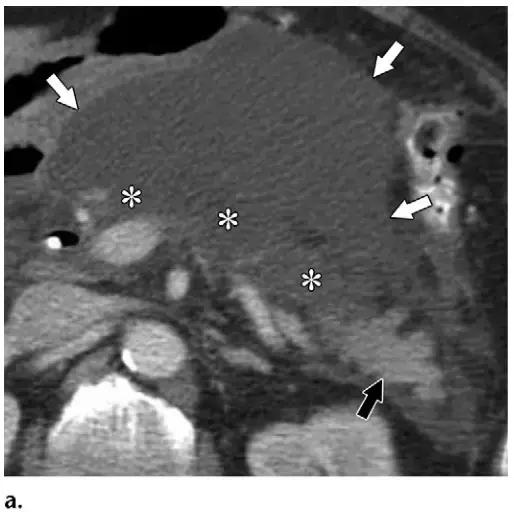

同时受累的亚型:表现为胰腺及胰周无强化坏死物,多累及小网膜囊和肾前间隙(图 3a)。

胰周型:表现为胰腺强化正常,而胰周坏死,坏死物可包括不等量的液体和和非液性成分,约占坏死性胰腺炎的 20%(图 3b)。

图 3 坏死性胰腺炎亚型在增强轴位 CT 的表现。a 胰腺和胰周同时受累的 58 岁女性患者,胰体无强化(*),正常强化的胰尾(黑箭头),小网膜囊内 ANC(白箭头)。b 仅胰周受累的 18 岁男性患者,可见一周为大片不均质密度(箭头),和 ANC 相符。胰腺实质密度正常(*)。c 仅胰腺实质受累的 33 岁男性患者,可见大片局限无强化的胰腺实质和脂肪密度(*),诊断为 WON。仅周边可见少量残余强化的胰腺实质(箭头)